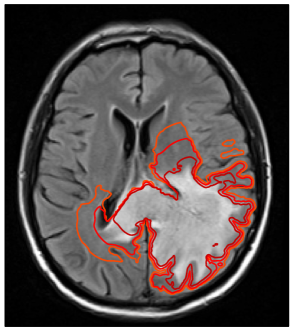

3.1 Target volume definition

Figure 4 shows the clinical target volume (dark green contour) and the boost volume (green contour) drawn manually by the physician, i.e. these contours were the basis for the treatment plan that was actually delivered to the patient. The prescribed dose to the boost volume was 60 Gy, the prescribed dose to the CTV was 46 Gy. The boost volume is defined based on a 2 cm isotropic extension of the contrast enhancing lesion. The CTV is defined via a 1.5 cm expansion of the T2-FLAIR abnormality. Both volumes were subsequently trimmed manually to account for anatomical boundaries (dura, ventricles, falx, and tentorium cerebelli). The dose distribution of the 3D conformal treatment plan delivered to the patient is shown in figure 6d.

Using the tumor growth model, the target volume can be defined as an isoline of the tumor cell density. This is illustrated here for the tumor cell density shown in figure 3a obtained for the parameter value Dw/Dg=100subscript𝐷𝑤subscript𝐷𝑔100D_{w}/D_{g}=100. The red and the orange contours in figure 4 show the CTV and the boost volume derived from the tumor growth model, respectively. In this example, the target defining isolines are chosen such that the total enclosed volume is equal to the manually delineated target. In the following two subsections, we discuss the differences between manual and model-derived target volumes in detail.

Refer to caption

Figure 4: Comparison of manually defined targets (light/dark green) and model derived targets (orange/red). In the clinical treatment plan, the light green volume was prescribed to 60 Gy, the dark green volume to 46 Gy. The yellow contour shows the abnormality on T2-FLAIR.

3.4 Difference in target volumes

In order to quantitatively compare the difference of manual and model-derived target volumes, we calculate the Dice coefficient, which is given by the volume where both structures overlap, divided by the average volume of the two structures. For the boost and CTV volumes in figure 4 the Dice coefficients are 0.78 and 0.77, respectively. Thus, three quarters of the manual target is also contained in the model-derived target, but a substantial portion of approximately one quarter is different.